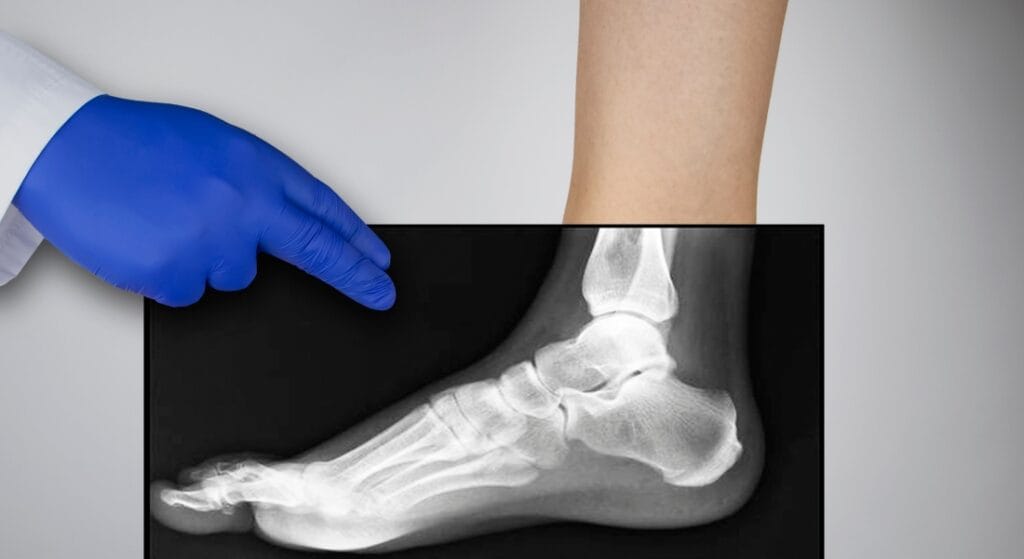

X-quang là kỹ thuật sử dụng tia bức xạ X – một dạng sóng điện từ có năng lượng cao – để tạo ra hình ảnh bên trong cơ thể. Khi chiếu qua các mô và cơ quan, tia X bị hấp thụ ở các mức độ khác nhau. Xương, răng – chứa nhiều canxi – hấp thụ tia mạnh hơn nên hiện lên màu trắng; trong khi mô mềm và khí hấp thụ ít hơn, tạo nên hình ảnh mờ đậm nhạt khác nhau.

Chụp X-quang là một trong những phương pháp chẩn đoán hình ảnh được sử dụng phổ biến nhất hiện nay. Với khả năng ghi lại hình ảnh bên trong cơ thể, X-quang giúp bác sĩ phát hiện nhanh chóng và chính xác nhiều bệnh lý liên quan đến xương khớp, phổi, tim mạch, răng hàm mặt… Tuy nhiên, nhiều người lo ngại việc chụp X-quang nhiều lần có thể ảnh hưởng đến sức khỏe và thường đặt câu hỏi: “Khoảng cách giữa 2 lần chụp X-quang là bao lâu? Liệu chụp nhiều có gây hại không?”